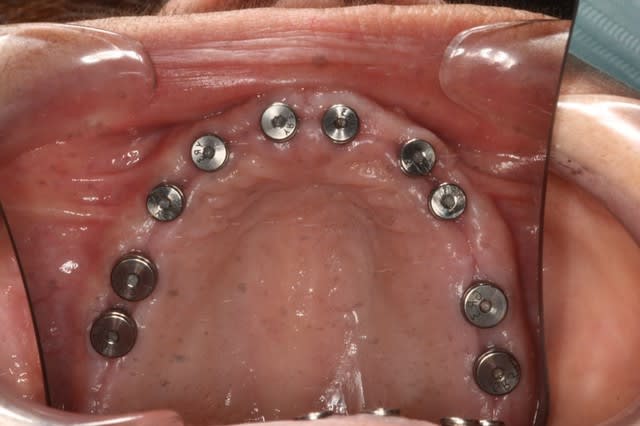

Exo + greffes + implants (axe et position idéaux, à la Misch) Planif 3D

(10 en haut et 8-10 en bas)

Bridges sur implants

Le même cas, patiente de 48 ans, paro ,mobilité, stellittes, occlusion moche, bref, rien de bon.

Bon j'aurais pu en placer 10 en bas...mais bon...